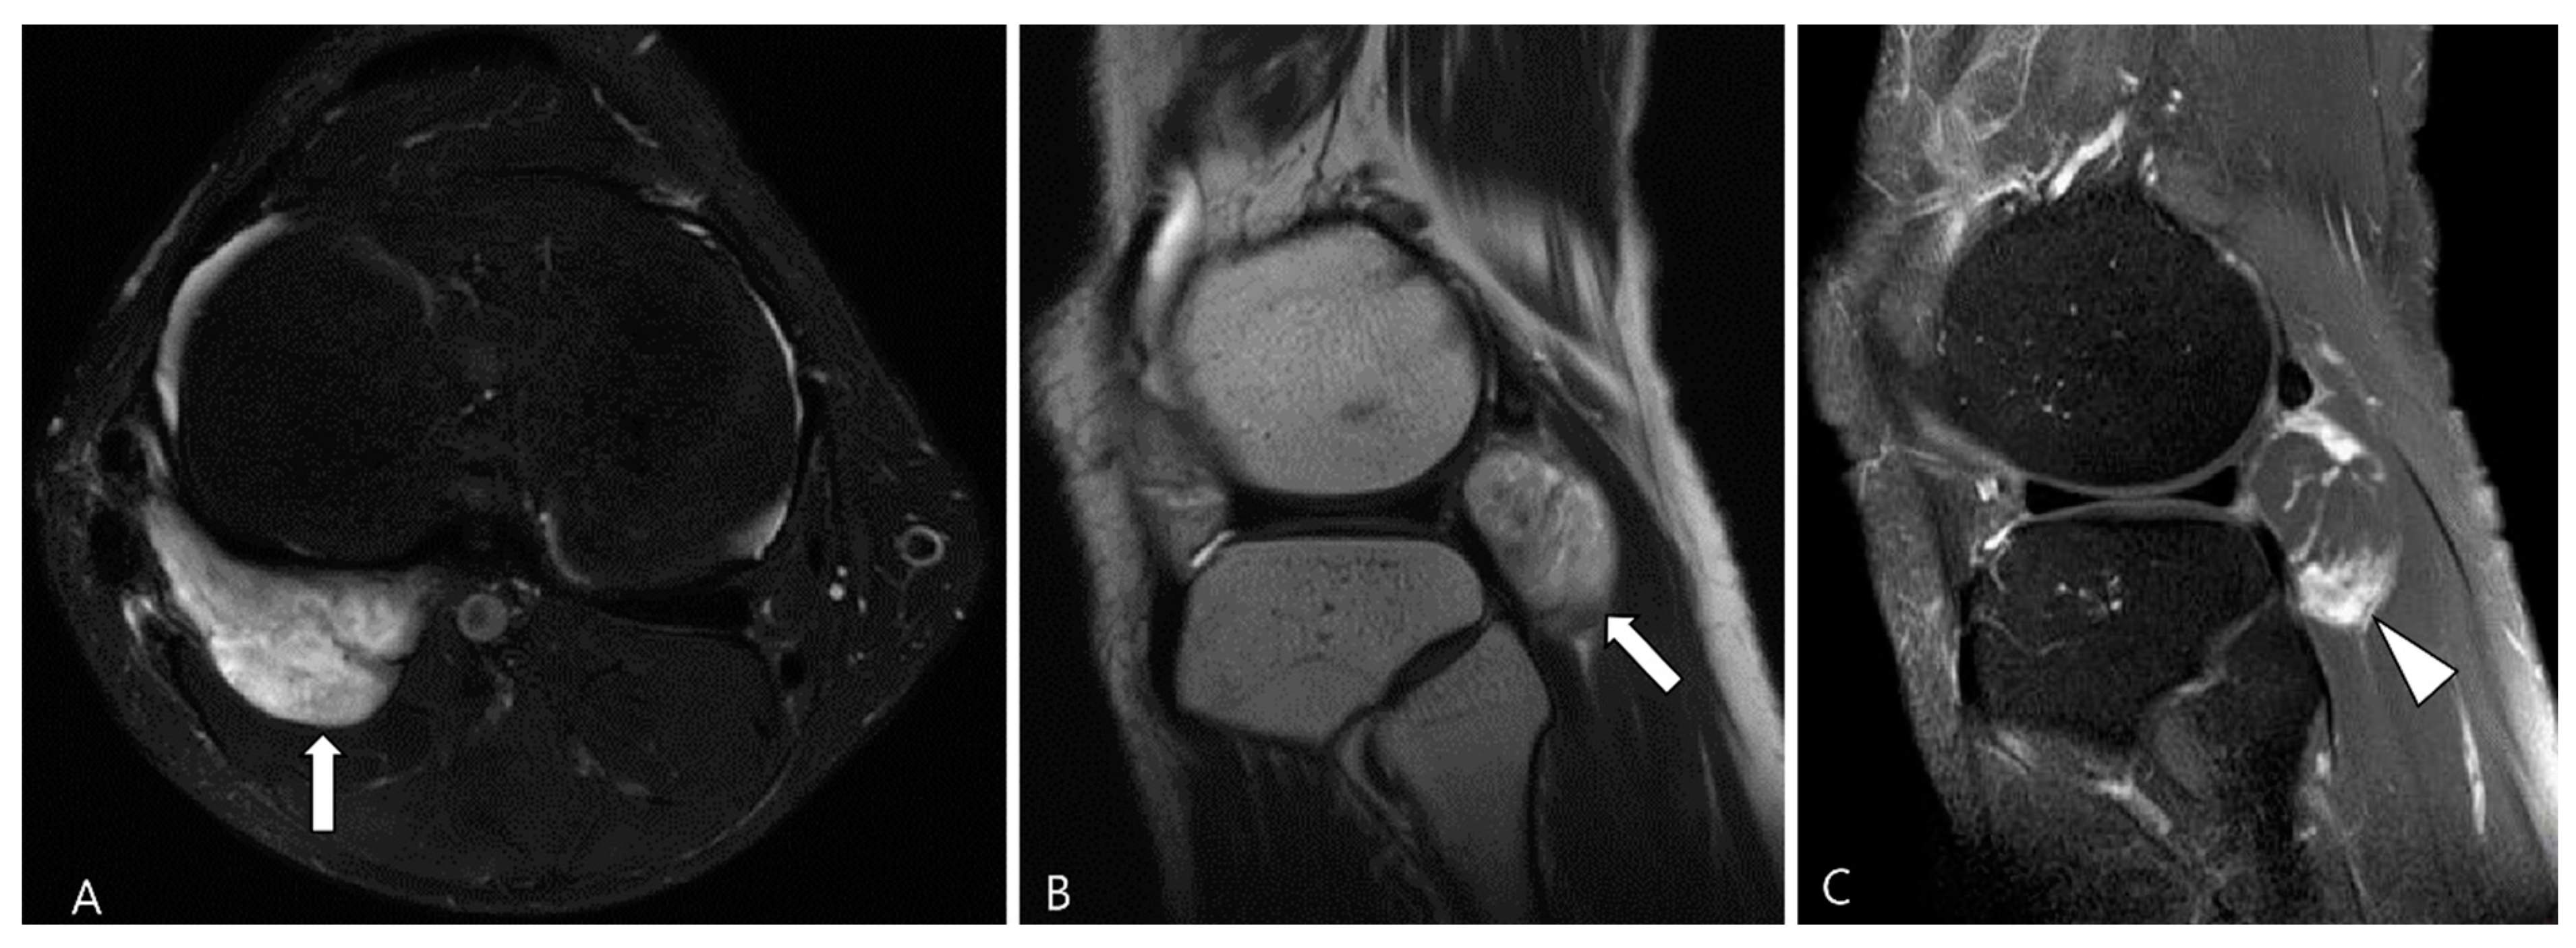

3.2.2. Extra-Abdominal Desmoid-Type Fibromatosis (DF)

- Okuda, M.; Yoshida, K.; Kobayashi, S.; Gabata, T. Desmoid-type fibromatosis: Imaging features and course. Skeletal Radiol. 2023, 52, 1293–1303. [Google Scholar] [CrossRef] [PubMed]

- Ganeshan, D.; Amini, B.; Nikolaidis, P.; Assing, M.; Vikram, R. Current Update on Desmoid Fibromatosis. J. Comput. Assist. Tomogr. 2019, 43, 29–38. [Google Scholar] [CrossRef] [PubMed]

- McDonald, E.S.; Yi, E.S.; Wenger, D.E. Best cases from the AFIP: Extraabdominal desmoid-type fibromatosis. Radiographics 2008, 28, 901–906. [Google Scholar] [CrossRef]

- Rosa, F.; Martinetti, C.; Piscopo, F.; Buccicardi, D.; Schettini, D.; Neumaier, C.E.; Gandolfo, N.; Grazioli, L.; Gastaldo, A. Multimodality imaging features of desmoid tumors: A head-to-toe spectrum. Insights Imaging 2020, 11, 103. [Google Scholar] [CrossRef]